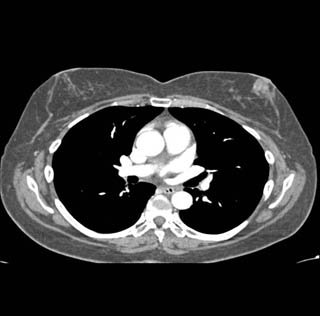

Diagnostic Case Quiz ❯ Anatomical Region Quiz: Chest

The best dx in this case is?

lung cancer

lymphoma

breast cancer

melanoma